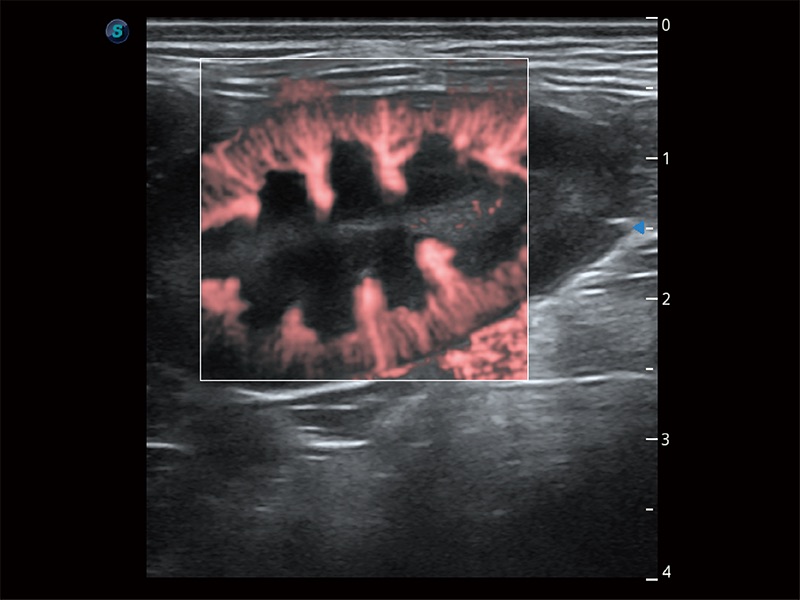

操作簡(jiǎn)便,無(wú)需高頻度外力作用即可真實(shí)反映組織的形變,快速評(píng)估腫瘤良惡性。

非線性融合造影成像充分利用諧波和基波信號(hào),為難以觀察的血流進(jìn)行增強(qiáng)顯像??捎糜诰€陣、凸陣、微凸陣、相控陣探頭。